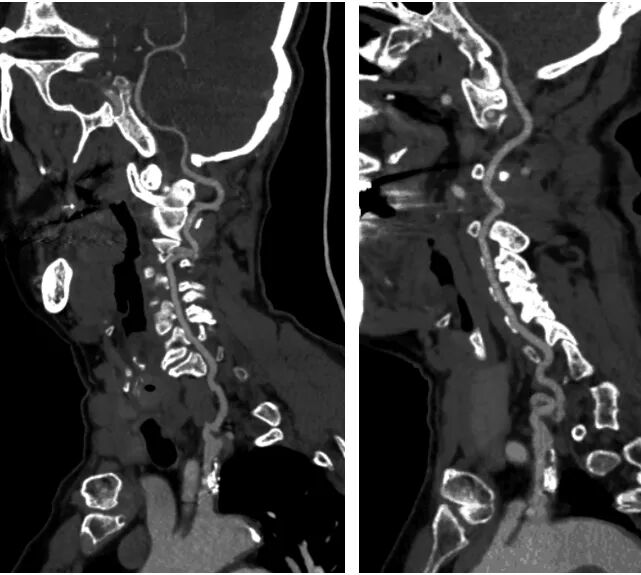

病例二

· 病例介绍

▪患者,女,71岁;

▪“反复头晕2月余”入院;

▪CTA:左侧锁骨下动脉起始部重度狭窄;

▪TCD:锁过下动脉盗血。

·右侧桡动脉入路造影

明确左侧锁骨下动脉起始部重度狭窄;

同时发现起始部斑块为溃疡斑块。

·球扩后植入9-30自膨颈动脉支架